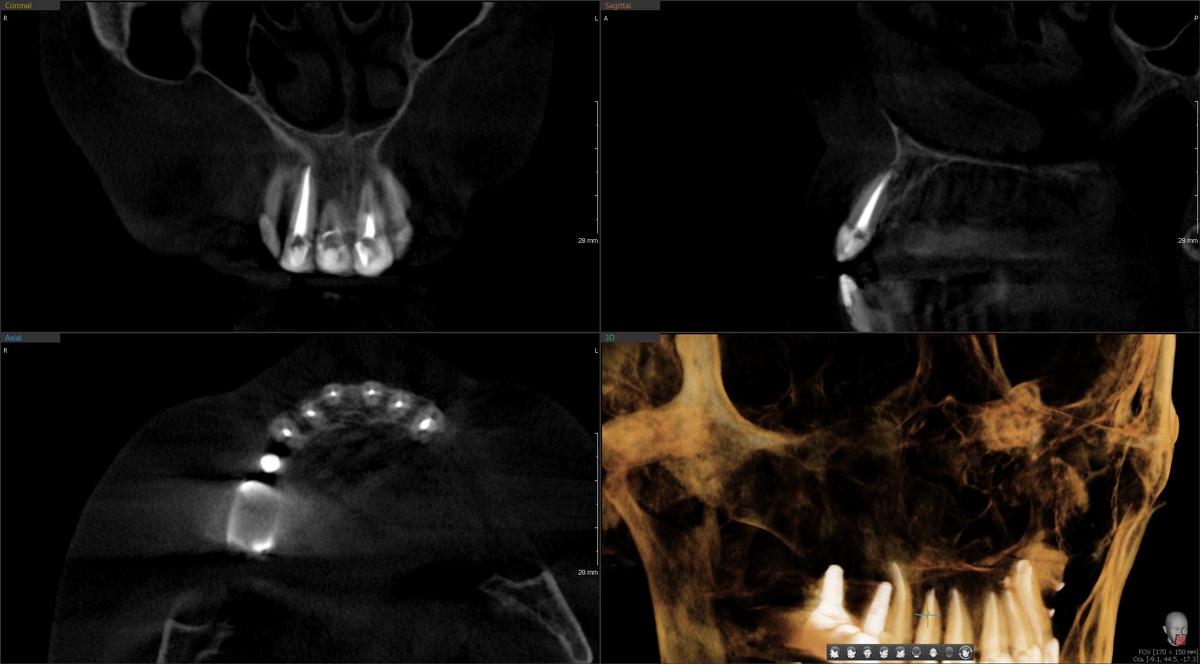

Сделали КТ.

На верхушке корня визуализировался совсем небольшой очаг деструкции костной ткани. Диагноз "периодонтит" ставим. В целом же - зуб как зуб. Ничего катастрофического на первый взгляд.

Но кое-что смущало. Точка неприятных ощущений располагалась не у верхушки, а будто бы по центру проекции корня на десне. Не совсем типично для апикального периодонтита. На КТ в этой зоне ничего не видно - гуттаперча засвечивала всё вокруг, как это часто и бывает.